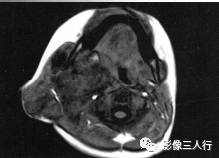

A.B.MRI T1WI显示右侧上颈部大片混杂低信号,其内见蜂窝状更低信号,肌间隙显示不清,并见点、线状高信号。咽、喉、气管受压移位;C〜F.T2WI的横断面、冠状面病变表现为不均匀高信号,形态不规则,可见病变向上、下,向左、右延伸,有“见缝就钻”的特点,气管及周围软组织受压移位

2.T1WI显示右侧颈部大片混杂低信号,其内见到多个类圆形囊性低信号。

3.T2WI病变表现为不均匀的高信号,形态不规则,其内可见分隔,具有“见缝就钻”的特点。气管及周围软组织受压移位。